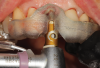

Dynamic navigation is not limited to the drilling of implant osteotomies. Surgical devices, such as piezo surgical units, can be used for sinus window access, bone plate harvesting, ridge splitting, bone reduction, and more. High-speed and low-speed handpieces, as well as subsequent drills, can be calibrated and used to plan specific surgical procedures, such as partial extraction therapy (Figure 4),8 a technique that involves retaining a fragment of tooth while preserving the remaining alveolar bone following tooth extraction.9,10

Fig 4. In partial extraction therapy, intentional

sectioning of a root leaves a fragment attached to the facial aspect to

preserve hard and soft tissue. An implant can be placed simultaneously

or in a delayed approach.

Figure 4